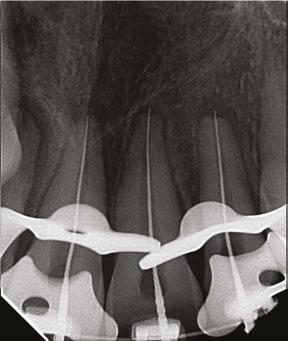

Two days after treatment, the patient was seen in my practice after the teeth were splinted back in place by the orthodontist. Figures 2A-2B are the preoperative radiographs after the teeth were reimplanted.

One can already appreciate the inflammatory resorption that is occurring at the apices of teeth Nos. 9 and 10. These images were taken just two days after the trauma.

Figures 2A-2B